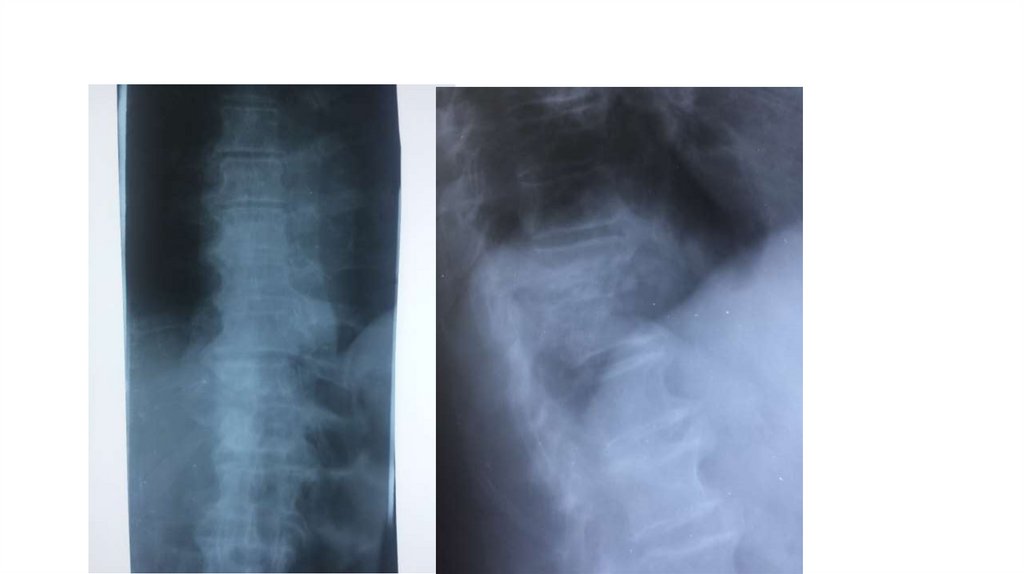

«Воспалительные

заболевания опорнодвигательного аппарата»